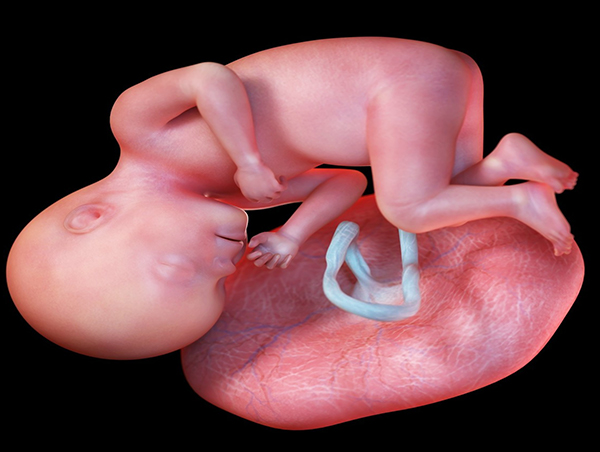

孕晚期经常走路是不会导致胎盘前置的,只是需要注意不要一次性走太多路,可以走一会休息一会,身边一定要有人陪同才行。导致胎盘前置的原因有很多,到目前为止还没有一个统一的定论,但是可以肯定的是,胎盘前置与其走路并没有太大关系,所以无需担心。胎盘前置的主要原因正常胎盘附着于子宫体部的后壁、前壁或侧壁。若胎盘附着于子宫下段,甚至胎盘下缘达到或覆盖宫颈内口处,其位置低于胎儿先露部,称为前置胎盘。临床按胎盘与子...